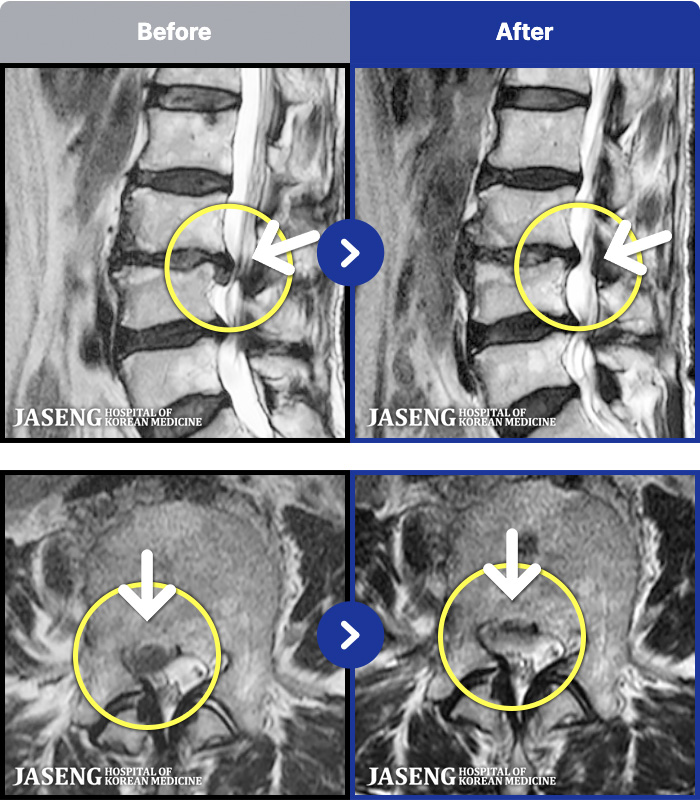

- MRI ġ

MRI ġ

191 MRI ũ ʸ Ȯϼ.

[_㸮ũ] 㸮 ٸ ϰ ϻȰ Ұ߽ϴ.